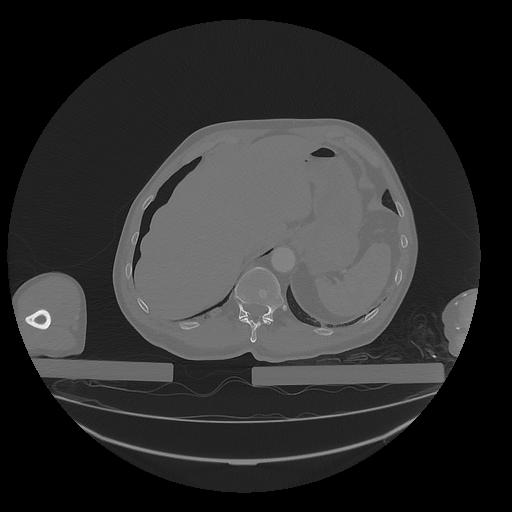

31 PULMON,CE,Vol,1.0,PULMON,,